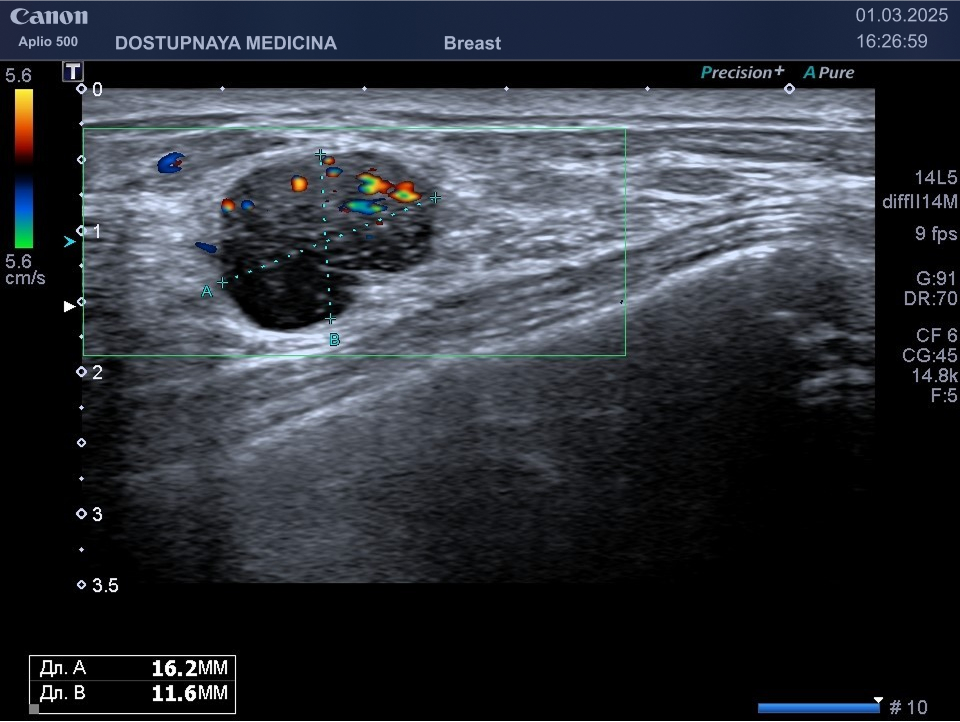

Кисты могут воспаляться, тогда при ультразвуковом исследовании в режиме ЦДК вокруг кисты отмечается усиление кровотока, пациентка при этом жалуется обычно на уплотнение и боль в области кисты молочной железы. Воспаление кисты может привести к её абсцедированию.

При ультразвуковом исследовании в кисте может быть визуализирован папиллярный компонент с кровотоком в режиме ЦДК. Так могут выглядеть цистаденопапилломы, которые считаются аблигатным предраком.